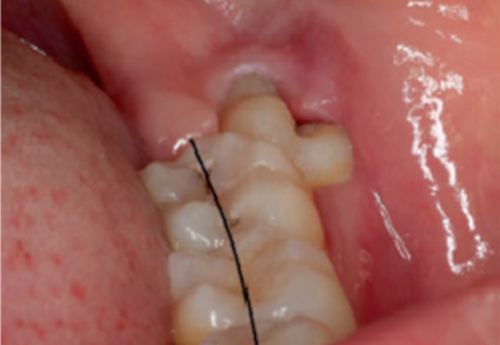

Protiniai dantys – tai tretieji krūminiai dantys, kurie pradeda kaltis 17-25 metų žmonėms. Kartais šie dantys išdygsta nesukeldami jokio diskomforto, tačiau dalis pacientų skundžiasi dantenų paburkimu ar skausmu – neretai taip nutinka dėl to, kad protinių dantų dygimui neužtenka vietos arba protinis dantis yra netaisyklingos padėties. Protinių dantų dygimo laikotarpiu rekomenduojama skalauti burną sūriu vandeniu – tai sumažins skausmą ir neleis atsirasti bakterijoms. Taip pat galima ant vatos tamponėlio užlašinti eterinio gvazdikėlių aliejaus ir uždėti ant skaudamos vietos. Ilgainiui skausmas turėtų praeiti, tačiau kartais nutinka ir taip, kad vos tik susiformavusius protinius dantis tenka rauti – ši chirurginė intervencija neretai skiriama tada, kai protiniai dantys negali tinkamai prasikalti ar kuomet jų padėtis nėra taisyklinga.